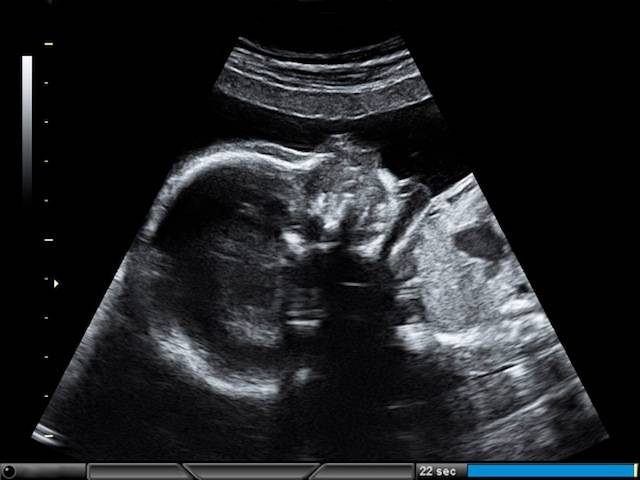

Leggere le ecografie in gravidanza: come capire se è maschio o femmina

Quando si è incinte praticamente ogni mese si viene sottoposte ad un’ecografia. Le più importanti sono le prime in cui si ...